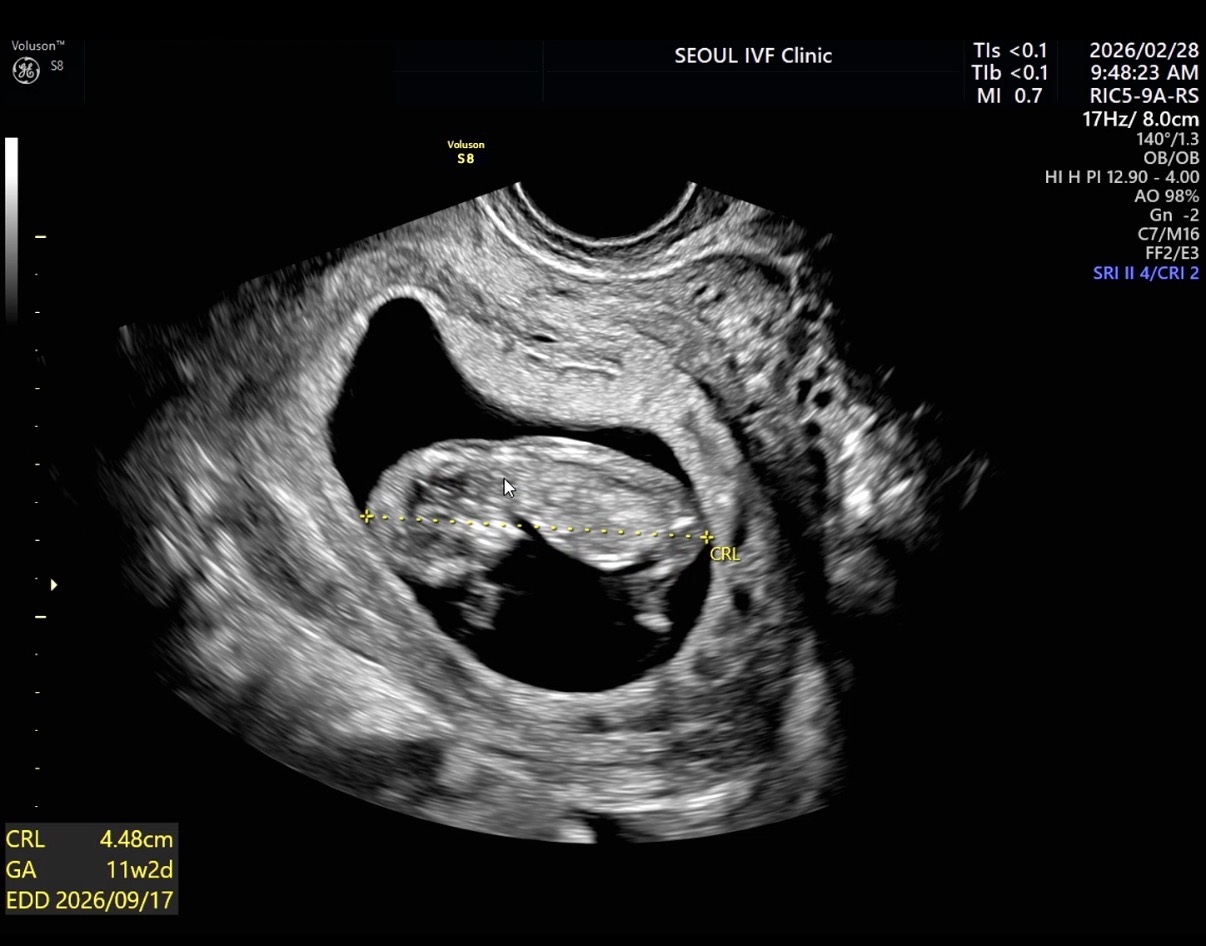

| 가슴 떨리는 임신 이야기를 공유해 주세요. | 시험관 시술 2차를 진행한 후에도 별다른 증상이 없어 이번에도 아닐 거라고 생각하고 있었습니다. 그런데 피검사 결과에서 임신이라는 이야기를 들었을 때, 말이 나오지 않을 정도로 얼떨떨했고 동시에 설레는 감정을 느꼈습니다. |